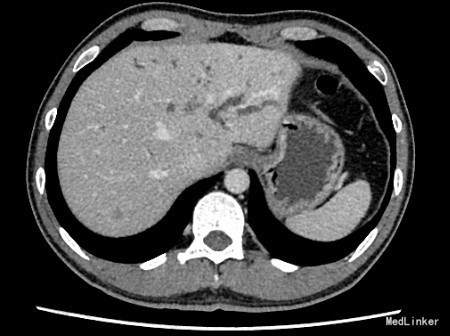

查体:身目重度黄染,上腹部轻压痛; 辅助检查: 白细胞WBC:10.96; 血红蛋白Hb:145g/L;血小板PLT:241x10^9/L 丙氨酸氨基转移酶ALT 357 U/L ;天冬氨酸氨基转移酶AST 191 U/L;白蛋白ALB 40.9 g/L ;总胆红素TBIL 151.2 umol/L;直接胆红素DBIL 85.8 umol/L 肿瘤标记物: 甲胎蛋白(AFP) 5.00 ug/L 0.00 - 20.00 ;癌胚抗原(CEA) 9.19 ug/L ↑ 0.00 - 5.00 ;CA125 71.00 U/mL ↑ 0.00 - 35.00 鳞癌抗原(SCC) 0.90 ug/L 0.00 - 1.50 ;CA19-9 〉12000.00 U/mL CT:平扫胰体尾部萎缩,胰头区不规则肿大,局部可见类圆形软组织肿块影,大小约44×43mm,边界模糊,内部密度不均,其内可见斑点状钙化灶,并见更低密度区。增强扫描正常胰腺组织明显强化而肿物轻度强化,显示较清楚;强化不均匀,中央有低密度坏死区。肿块与十二直肠降段分界不清,病变包绕肠系膜上静脉,血管见充盈缺损影,胰头周围及腹膜后见肿大的淋巴结影。、、、 1.胰头癌,侵犯十二指肠降段及肠系膜上静脉,胰周及腹膜后多发淋巴结轻度肿大。 2.肝S7病灶,高度怀疑转移瘤。 超声造影提:胰头病变:考虑胰头Ca。 肝S7病变:考虑MLC。 肝内外胆管弥漫性扩张。胆囊壁增厚。腹膜后淋巴结肿大。脾脏超声检查未见异常。